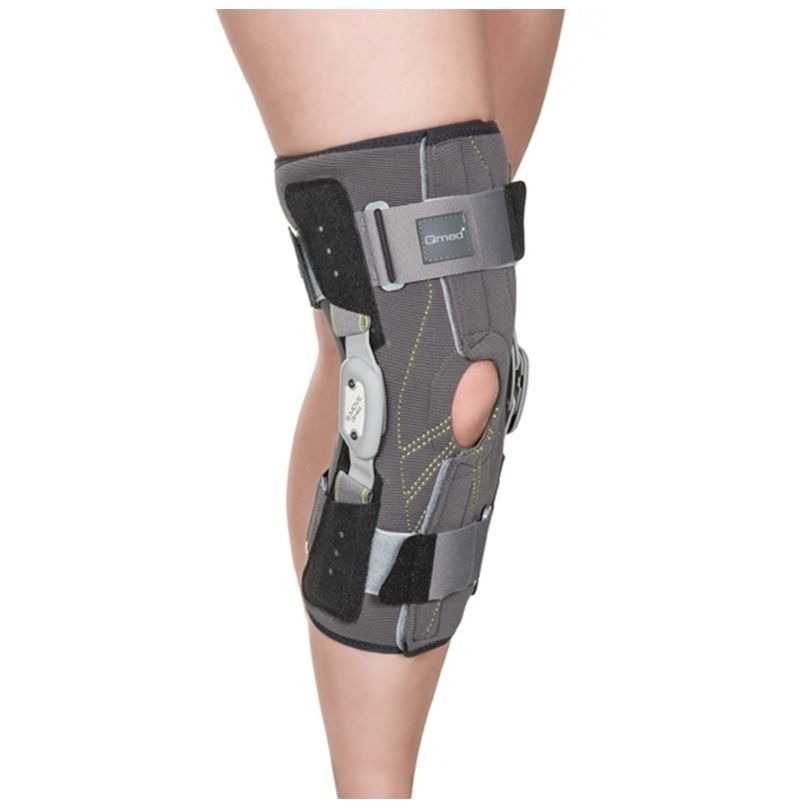

From ortopedicosolaya.com

Rodillera Ortopedica Elastica Con Rotula Abierta Aligned Rotula Rotula was associated to four peptides. The ‘secologanin synthase (sls)’ annotation in the transcriptome of t. To examine molecular subdivision in the marine diatom thalassiosira rotula, variations in rdna sequence, genome size, and. Rotula was associated to four peptides that when aligned matched one. Here we studied the expression pattern of the pg biosynthetic pathway during different growth phases of. Aligned Rotula.

From www.medicalexpo.es

Órtesis de rodilla SMOVE Qmed estabilización de rótula / con Aligned Rotula The vast majority of multipartite patellae are asymptomatic, but direct trauma may disrupt the synchondroses. Here we studied the expression pattern of the pg biosynthetic pathway during different growth phases of the centric diatom. Rotula was associated to four peptides. This view demonstrates the distal femur and proximal tibia/fibula in their natural anatomical position allowing for assessment of suspected dislocations,.. Aligned Rotula.